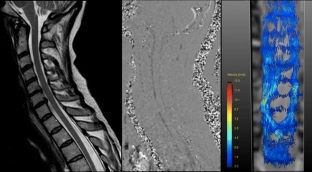

The 4D PC sequence allowed for flow quantification and visualisation in all individuals. Bland-Altman analysis showed good agreement of 2D and 4D PC velocity data. In healthy volunteers, CSF flow was homogeneously distributed in the anterior and anterolateral subarachnoid space with the flow directed caudally during systole and cranially during diastole. Flow velocities were closely related to the width of the subarachnoid space. Patients showed grossly altered CSF flow patterns with formation of flow jets with increased flow velocities.

4D PC MR imaging allows for a detailed assessment of CSF flow dynamics helping to distinguish physiological from complex pathological flow patterns at the craniocervical junction and the cervical spine.